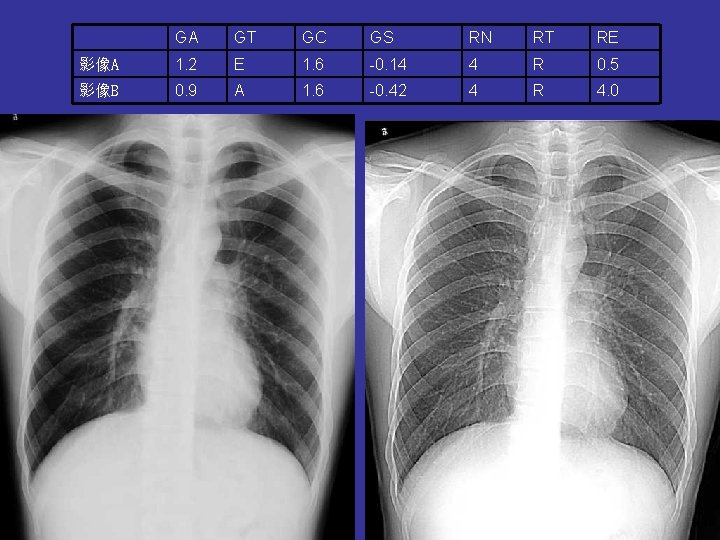

GA GT GC GS RN RT RE 影像A 1. 2 E 1. 6 -0. 14 4 R 0. 5 影像B 0. 9 A 1. 6 -0. 42 4 R 4. 0